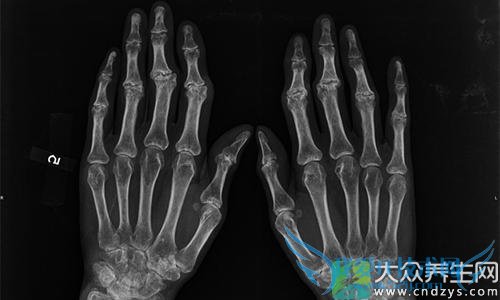

风湿性关节炎是一种常见的急性或慢性结缔组织炎症。可反复发作并累及心脏。临床以关节和肌肉游走性酸楚、重著、疼痛为特征。属变态反应性疾病。是风湿热的主要表现之一,多以急性发热及关节疼痛起病。

典型表现是轻度或中度发热,游走性多关节炎,受累关节多为膝、踝、肩、肘、腕等大关节,常见由一个关节转移至另一个关节,病变局部呈现红、肿、灼热、剧痛,部分病人也有几个关节同时发病。不典型的病人仅有关节疼痛而无其他炎症表现,急性炎症一般于2~4周消退,不留后遗症,但常反复发作。若风湿活动影响心脏,则可发生心肌炎,甚至遗留心脏瓣膜病变。